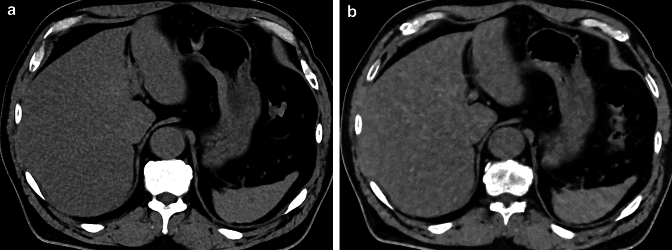

Fig. 7.

A true noncontrast CT image (A) and a virtual noncontrast CT image obtained from contrast-enhanced image data (B) acquired with photon-counting CT. Virtual noncontrast images with photon-counting CT have similar CT attenuation accuracy to true noncontrast images. In both images, the liver parenchyma is less attenuated than the spleen, indicating hepatic steatosis

Hepatic steatosis

Hepatic steatosis, including metabolic dysfunction-associated fatty liver disease and metabolic dysfunction-associated steatohepatitis, is a serious pathological condition of the liver that can progress to cirrhosis and hepatocellular carcinoma [39]. Estimation of intrahepatic fat is essential for the diagnosis of hepatic steatosis [40]. Photon-counting CT has been shown to be accurate for index-based liver fat estimation from virtual non-contrast images [41] and has the potential to increase the likelihood of incidental detection of liver steatosis on contrast-enhanced abdominal CT scans (Fig. 7). In addition, photon-counting CT can quantify intrahepatic fat even in the presence of iron overload [42].